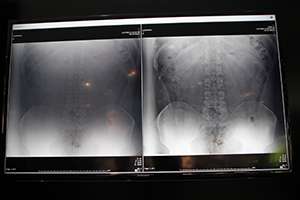

同社が行った胸部,腹部を想定したCD-RADファントムと人体を想定したアクリル板を用いた検証では,80kVでグリッドあり,グリッドなし,Virtual Gridでの計測を行ったところ,Virtual Gridでの低線量での画質の画質指数(IQF)が向上することが確かめられたという。展示では,Virtual Gridによる画質の向上の効果について,胸部や腹部の臨床画像を示して,実際の低線量撮影における画質の向上をアピールした。

Virtual Grid(右)による臨床画像(日本人の腹部) |

大柄なアメリカ人の腹部画像。 |